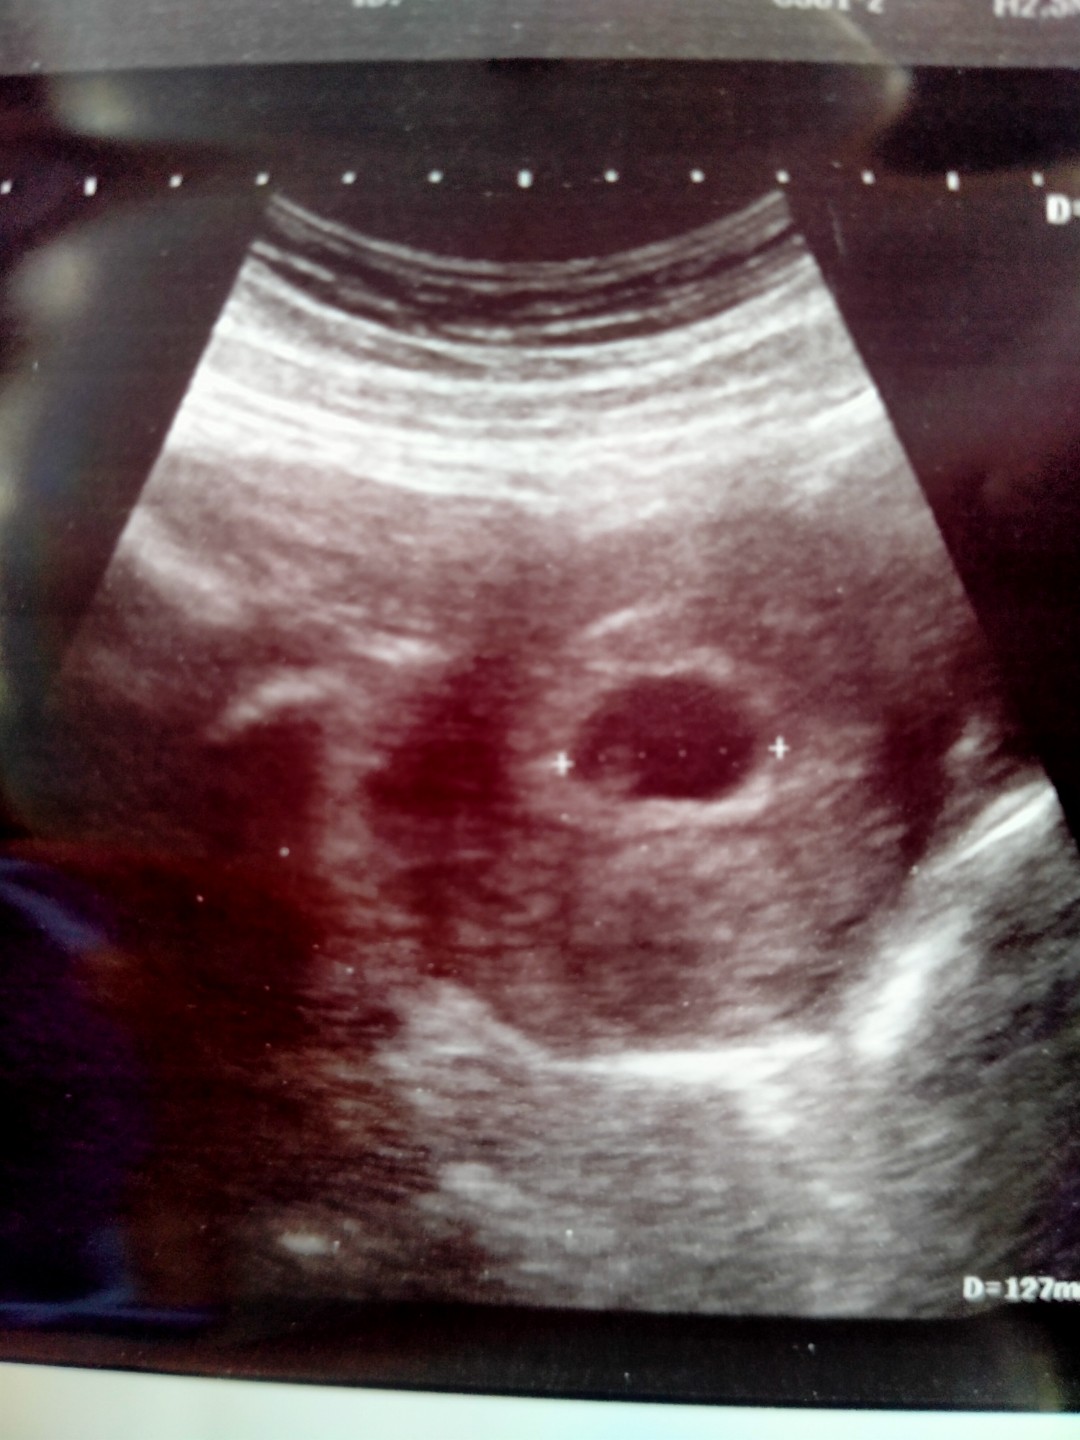

มีใครเป็นแบบนี้มั้ยคะ 7w พบแต่ถุงตั้งครรภ์ ไม่พบหัวใจเด็ก

อายุครรภ์ 7w อัลตร้าซาวด์เห็นแต่ถุงตั้งครรภ์ไม่พบหัวใจเด็ก อาทิตย์หน้าคุณหมอนัดขูดมดลูก

7w5d เพิ่งไปตรวจเมื่อเช้าที่คลีนิคมาค่ะ เจอแต่ถุงตั้งครรภ์ ส่วนเด็กไม่แน่ใจเพราะมันจาง หมอเลยนัดซาวอีก 2 สัปห์ดา ยังไม่ขูดจ้า ที่ต้องไปตรวจเพราะ แพ้ท้องอาทิตเดียว แล้วอาการแพ้ก็หายไปเฉยเลย กังวลมากเพราะเคยแท้งท้องแรก แต่ก็ไม่มีเลือดออกนะคะ

เหมือนกันเลยค่ะ6wกว่า ซาวด์ 2 รอบแล้วไม่เจอเลย หมอบอกว่าอาจจะยังเร็วเกินไป อาทิตย์หน้านัดอีกทีถ้ายังไม่เจอจะขอหมอรอดูจนถึง 10w ค่ะ กังวลมากเหมือนกันค่ะ เพราะอาการคนท้อง เช่น เจ็บนม คลื่นไส้ ปวดท้องจี๊ดๆ เริ่มหายไป

เราค่ะ มีเลือดออกแล้วไปหาคุณหมอ ถ้านับจากประจำเดือนก็จะครบ 7 w แต่พอซาวด์เจอแต่ถุงตั้งครรภ์ คุณหมอบอกให้ทำใจและนัดมาใหม่อีกอาทิตย์นึง พอ w ที่ 8 ซาวด์ใหม่ก็เจอหัวใจเด็กค่ะ

หมอได้ซาวในช่องคลอดรึเปล่าค่ะ เพราะตอนแม่เองก้ไม่เจอหัวใจ แต่พอซาวในช่องคลอดถึงเจอค่ะ ยังไงให้คุณหมอซาวทางช่องคลอดดีกว่านะคะ

บ้านนี้ตรวจ8wก้อไม่เจอค่ะไม่พบหัวใจเด็กเหมือนกัน เจอตอน11w คุนหมอบอกลองให้โอกาสเขาดูเพราะตัวยังเล็กมาก #สู้ๆค่ะอย่ากังวล✌

บ้านนี้ค่ะ 8 วีคไม่พบหัวใจ หมอนัดวีคที่9 เพื่อเหน็บยาและขูดมดลูก แต่พอซาวด์อีกทีพบหัวใจเด็กเลยไม่ได้ขูดค่ะ

มีค่ะ6วีคเจอถุงน้ำนิดเดียวหมอนัด8วีคเจอแต่ถุงหมอนัดอีกที10วีคถึงเจอหัวใจเด็กหมอนัดอีก12วีคถึงเจอเด็กค่ะ